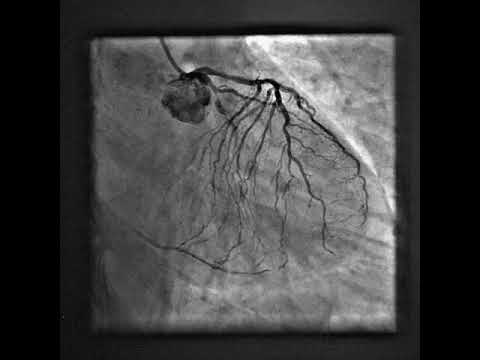

Interventional Treatment of Chronic Total Occlusion

Integrating New Therapies for Chronic Total Occlusion

complex multi vessel PCI.

Complex Multivessel PCI in a High SYNTAX Score Patient